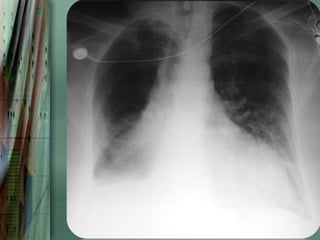

Radiography

Chest radiography is helpful in distinguishing CPE from other

pulmonary causes of severe dyspnea.

Features that suggest CPE rather than NCPE and other lung

pathologies include the following:

•   Enlarged heart

•   Inverted blood flow

•   Kerley lines

•   Basilar edema (vs diffuse edema)

•   Absence of air bronchograms

•   Presence of pleural effusion (particularly bilateral and

36

symmetrical pleural effusions)

37

38